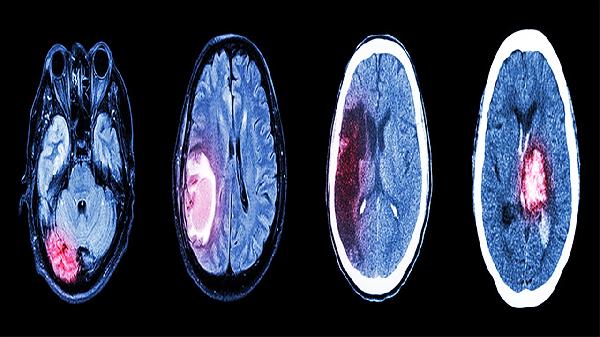

颅脑损伤的院前急救有哪些

颅脑损伤的院前急救包括保持呼吸道通畅、控制出血、固定头部和颈部,并尽快送往医院。急救过程中需避免移动患者头部,防止二次损伤,同时监测生命体征。